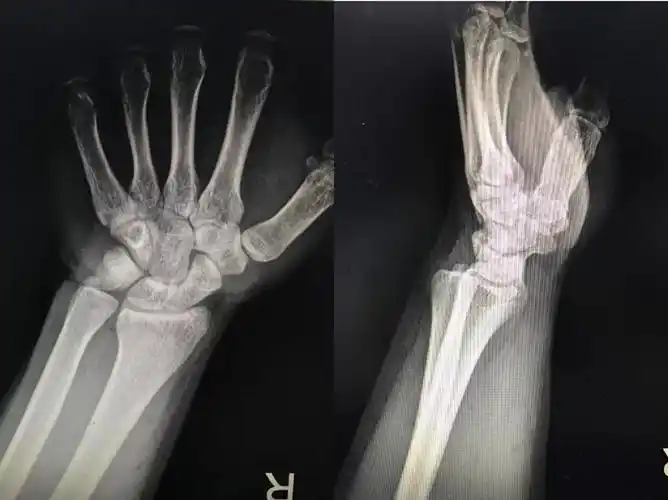

tfcc|腕关节|扭伤|疼痛|微创|-健康界